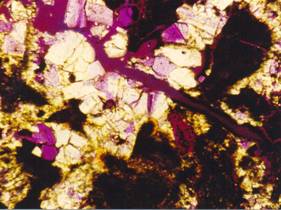

Krystalické agregáty Whewellitu s

výplní jemnozrnného apatitu.

Výbrus, polarizační mikroskop, zvětšeno 320x